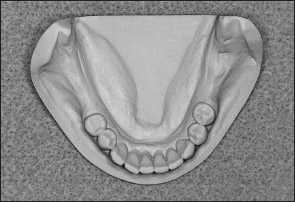

• Kennedy Class III arch: Presents a unilateral edentulous area with natural teeth both anterior and posterior to it (Figs 1-15 and 1-16).

Fig 1-15 Maxillary Kennedy Class III arch.

Fig 1-16 Mandibular Kennedy Class III arch.